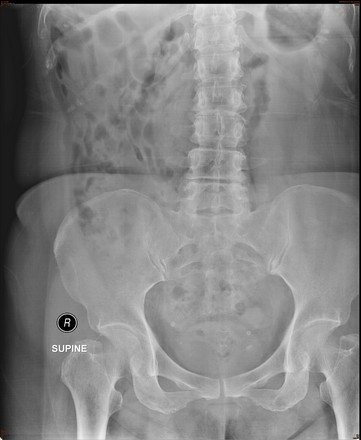

Plain abdominal film was performed on admission.

What is the abnormality?

Answer : C. Left distal ureteric stone or left distal vesicoureteric junction stone

Phleobolith

Stone

Radiographic Examination : Plain KUB

• Often used as an inexpensive first step -> 90% of urinary calculi are radiopaque

• However, while large calculi can easily be seen, confounding factors such as overlying bowel gas or fecal material and osseous structures